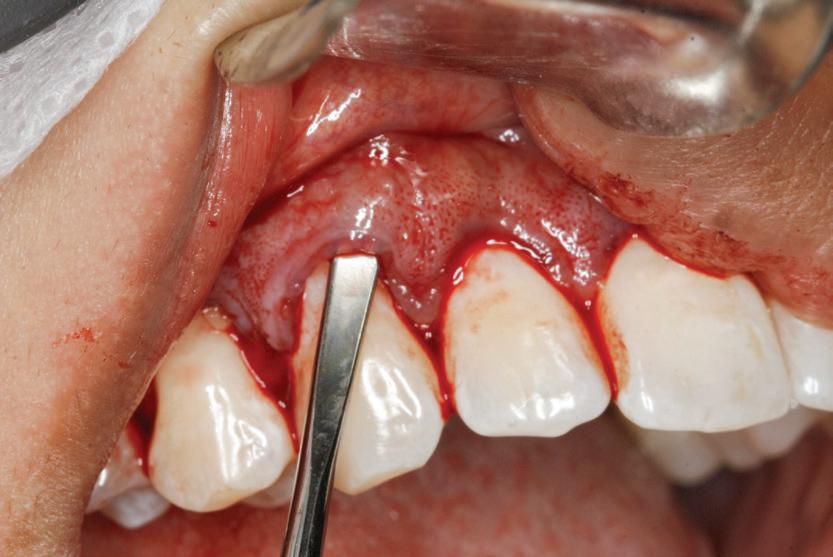

Expunerea deschisă

Se face o incizie semilunară înclinată cu o lamă 15 sau 15c de-a lungul porțiunii mezio-palatinale a dintelui, continuând disto-palatinal, cu o direcție conică către os. Cu ajutorul elevatoarelor periostale, se decolează un lambou cu grosime totală. Îndepărtarea osoasă se finalizează cu chiurete și instrumente rotative. Foliculul este îndepărtat cu grijă și se expune caninul suficient pentru a permite poziționarea corectă a bracketului. Acesta se atașează de dinte, și de el se conectează un arc de sârmă. Sângerarea în zonă este controlată cu utilizarea anesteziei locale, cu ceară osoasă, sau tifon impregnat cu anestezic 1:50.000.

O nouă lamă 15c se utilizează pentru fenestrarea țesutului gingival în locația bracketului și pentru a crea o trapă care expune bracketul prin lamboul fixat cu suturi. Utilizarea unui pansament parodontal în zonă este opțională. Forțele ortodontice sunt aplicate 2 săptămâni mai târziu în cazurile în care se dorește o tracțiune directă. S-a sugerat permiterea erupției spontane către planul ocluzal după expunerea deschisă și

Figurile: 4. Accesoriu de tipul porții batante utilizat pentru tracționarea directă a unui canin palatinal gestionat cu expunere deschisă.

5. Expunerea deschisă a unui canin cu impactare palatinală; s-a utilizat o bară transpalatinală ca sursă de ancorare cu un braț extensibil conceput pentru tracțiune directă.

apoi direcționarea vestibulară a caninului (fig. 8, 9).